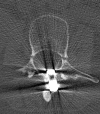

Case presentation: We report the case of a 46-year-old Caucasian woman who underwent surgery due to idiopathic scoliosis with a Harrington Instrumentation (T4 to L3) 30 years ago. During the operation she was infected with hepatitis C while receiving erythrocyte concentrates and has suffered from liver cirrhosis since then. She presented with a sudden pain in her lower back and paraesthesia in both her legs but no other neurological symptoms. A computed tomography scan showed a bilateral pedicle fracture of L3 and an additional compression fracture of L4. In the first session we performed a dorsal stabilization with massive intraoperative bleeding and a postoperative failure of liver synthesis. In a second session an additional ventral augmentation was done. After the second operation she developed a hepatorenal syndrome. Both operations left the patient in a very critical state which led to a prolonged stay in the intensive care and rehabilitation unit. At her 12-month follow-up visit, she was free of complaints.